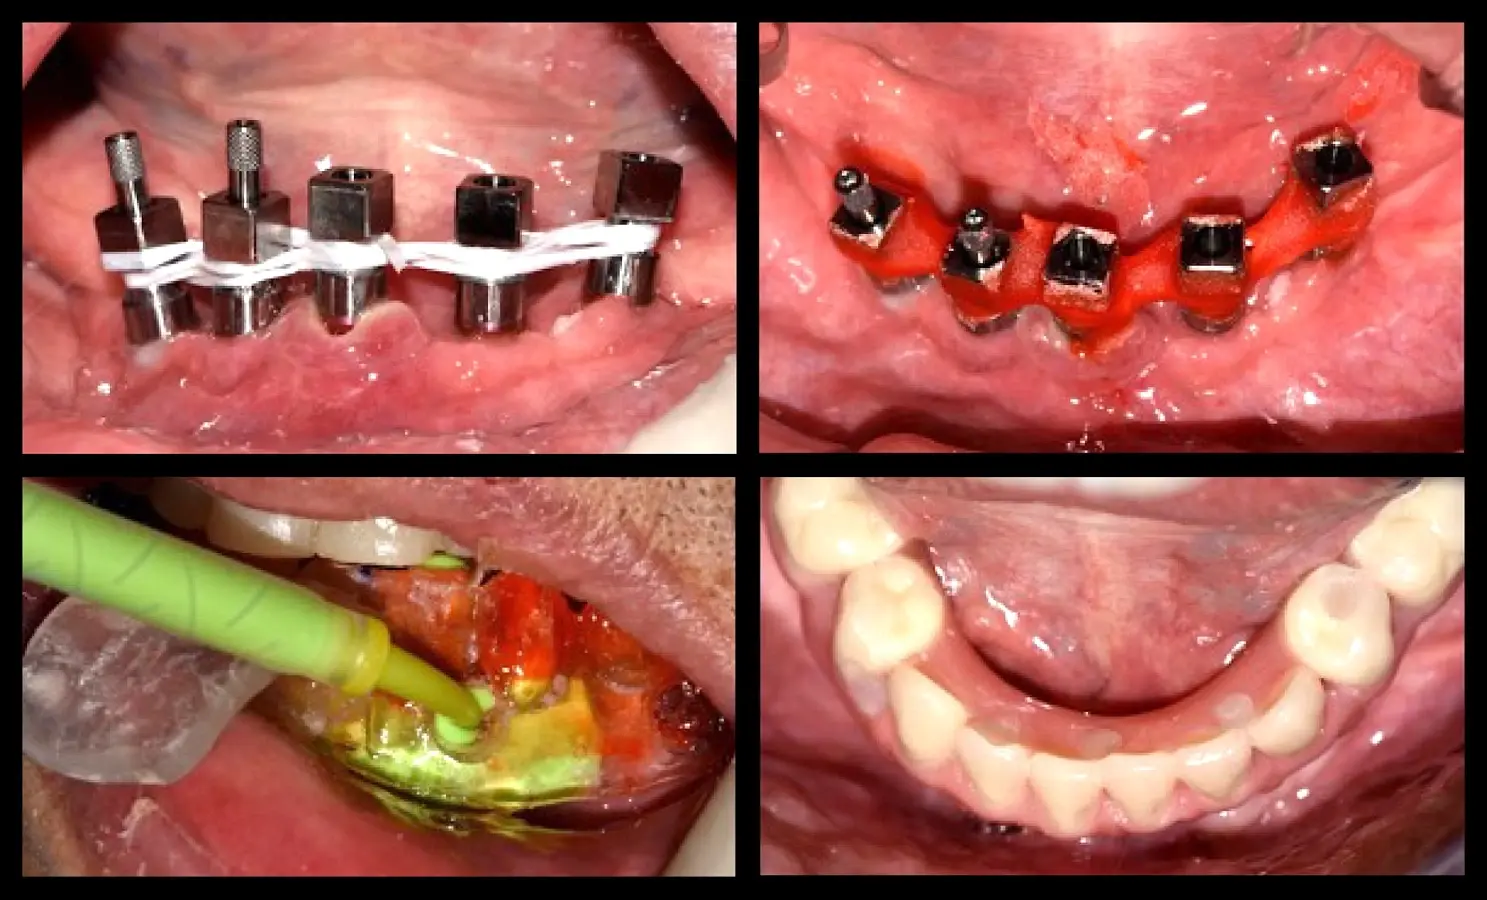

La segunda fase quirúrgica y colocación de pilares intermedios fue realizada en la semana 18, siguiendo la recomendación del fabricante con un torque de 20 Ncm. Se realizó la impresión del maxilar superior y la transferencia de los implantes del maxilar inferior. Una vez corroborado el asentamiento de ambas estructuras en boca se envió al laboratorio para el enfilado de la estructura inferior. Finalizada la prótesis fue instalada en el paciente (Figura 10).

Rehabilitación fina

Figura 10. Rehabilitación final: toma de impresión mediante la técnica de la guía multifuncional.